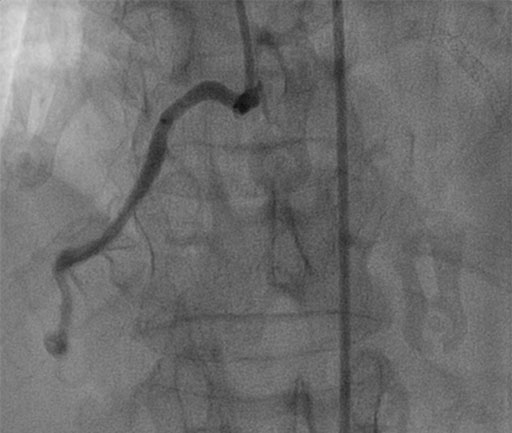

FFR of Cx

• COMET™ FFR wire delivers through highly tortuous vessel

• FFR of 0.88 (not pictured)

• Patient asymptomatic & ischemic territory is small

• No stents placed